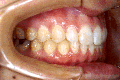

3.下顎前突(受け口) 下の歯が上の歯より出ています

治療前

上の八重歯が並んだ状態です